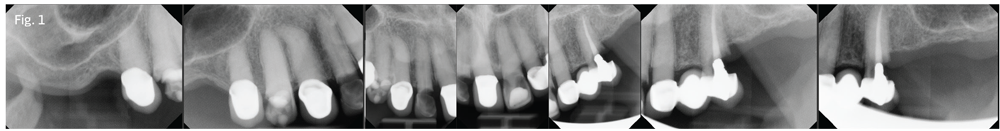

Figure 1

Visit #1: We gathered all diagnostic data—full-mouth radiographs (Fig. 1), preop photos (Fig. 2), CBCT scan (Fig. 3) and study model impressions. The patient was mildly sedated—30 milligrams of hydroxyzine slurry swallowed and 0.125mg triazolam crushed sublingually—and monitored with pulse oximeter throughout the treatment phase of the appointment.

After using Carbocaine 3% non-epinephrine local anesthetic to anesthetize the patient, I performed an atraumatic extraction for tooth #7, placed a 2.5-by-15mm implant (Fig. 4) and fabricated a temporary crown. I then switched my attention to the lower arch.

The patient's mandible was so resorbed that her lower denture did not fit in any usable way. I placed four mini-dental implants (2 by 10mm) with O-ball attachments (Fig. 4). I then cut away the posterior segments of the existing denture, leaving only the anterior six teeth to be used as a temporary, and processed the housings for the four mandibular implants into the anterior segment of the denture, using a self-cured denture base resin.